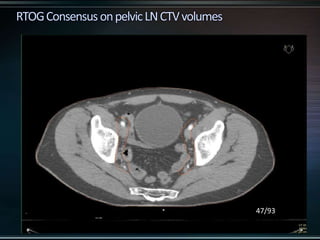

RTOG GU Consensus on pelvic LN CTV volumes:

 Commence contouring the pelvic CTV LN volumes at the L5/ S1

interspace (the level of the distal common iliac and proximal

presacral lymph nodes).

 Place a 7-mm margin around the iliac vessels connecting the

external and internal iliac contours on each slice, carving out

bowel, bladder, and bone.

 Contour presacral lymph nodes from S1 through S3, posterior

border being the anterior sacrum, and anterior border

approximately 10 mm anterior to the anterior sacral bone

carving out bowel, bladder, and bone.

 Stop external iliac CTV lymph node contours at the top of the

femoral heads (bony landmark for the inguinal ligament).

 Stop contours of the obturator CTV lymph nodes at the top of

the symphysis pubis.

45/93

47/93